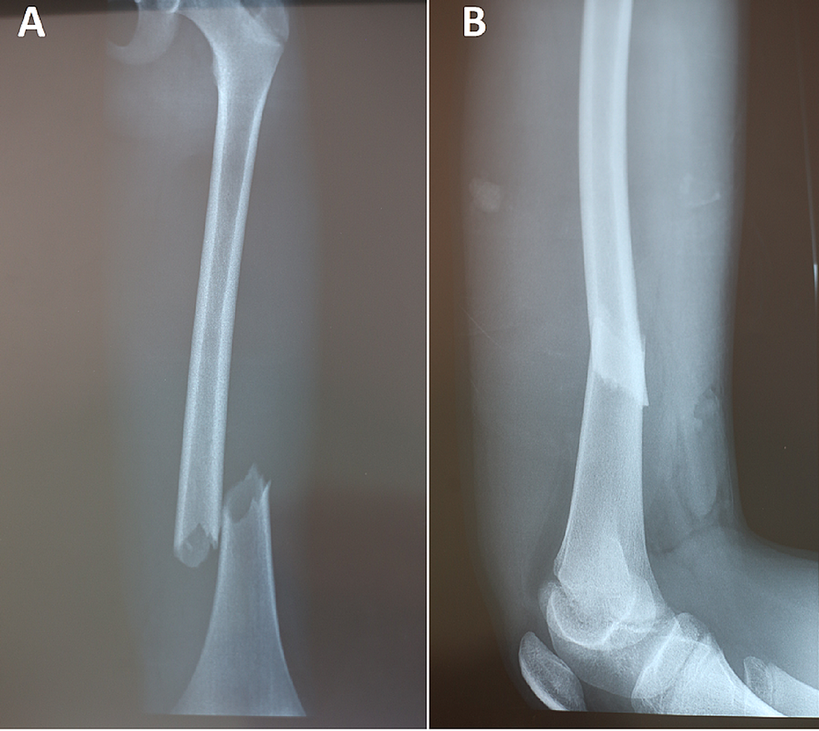

▲ 골절 capture cureus.com |